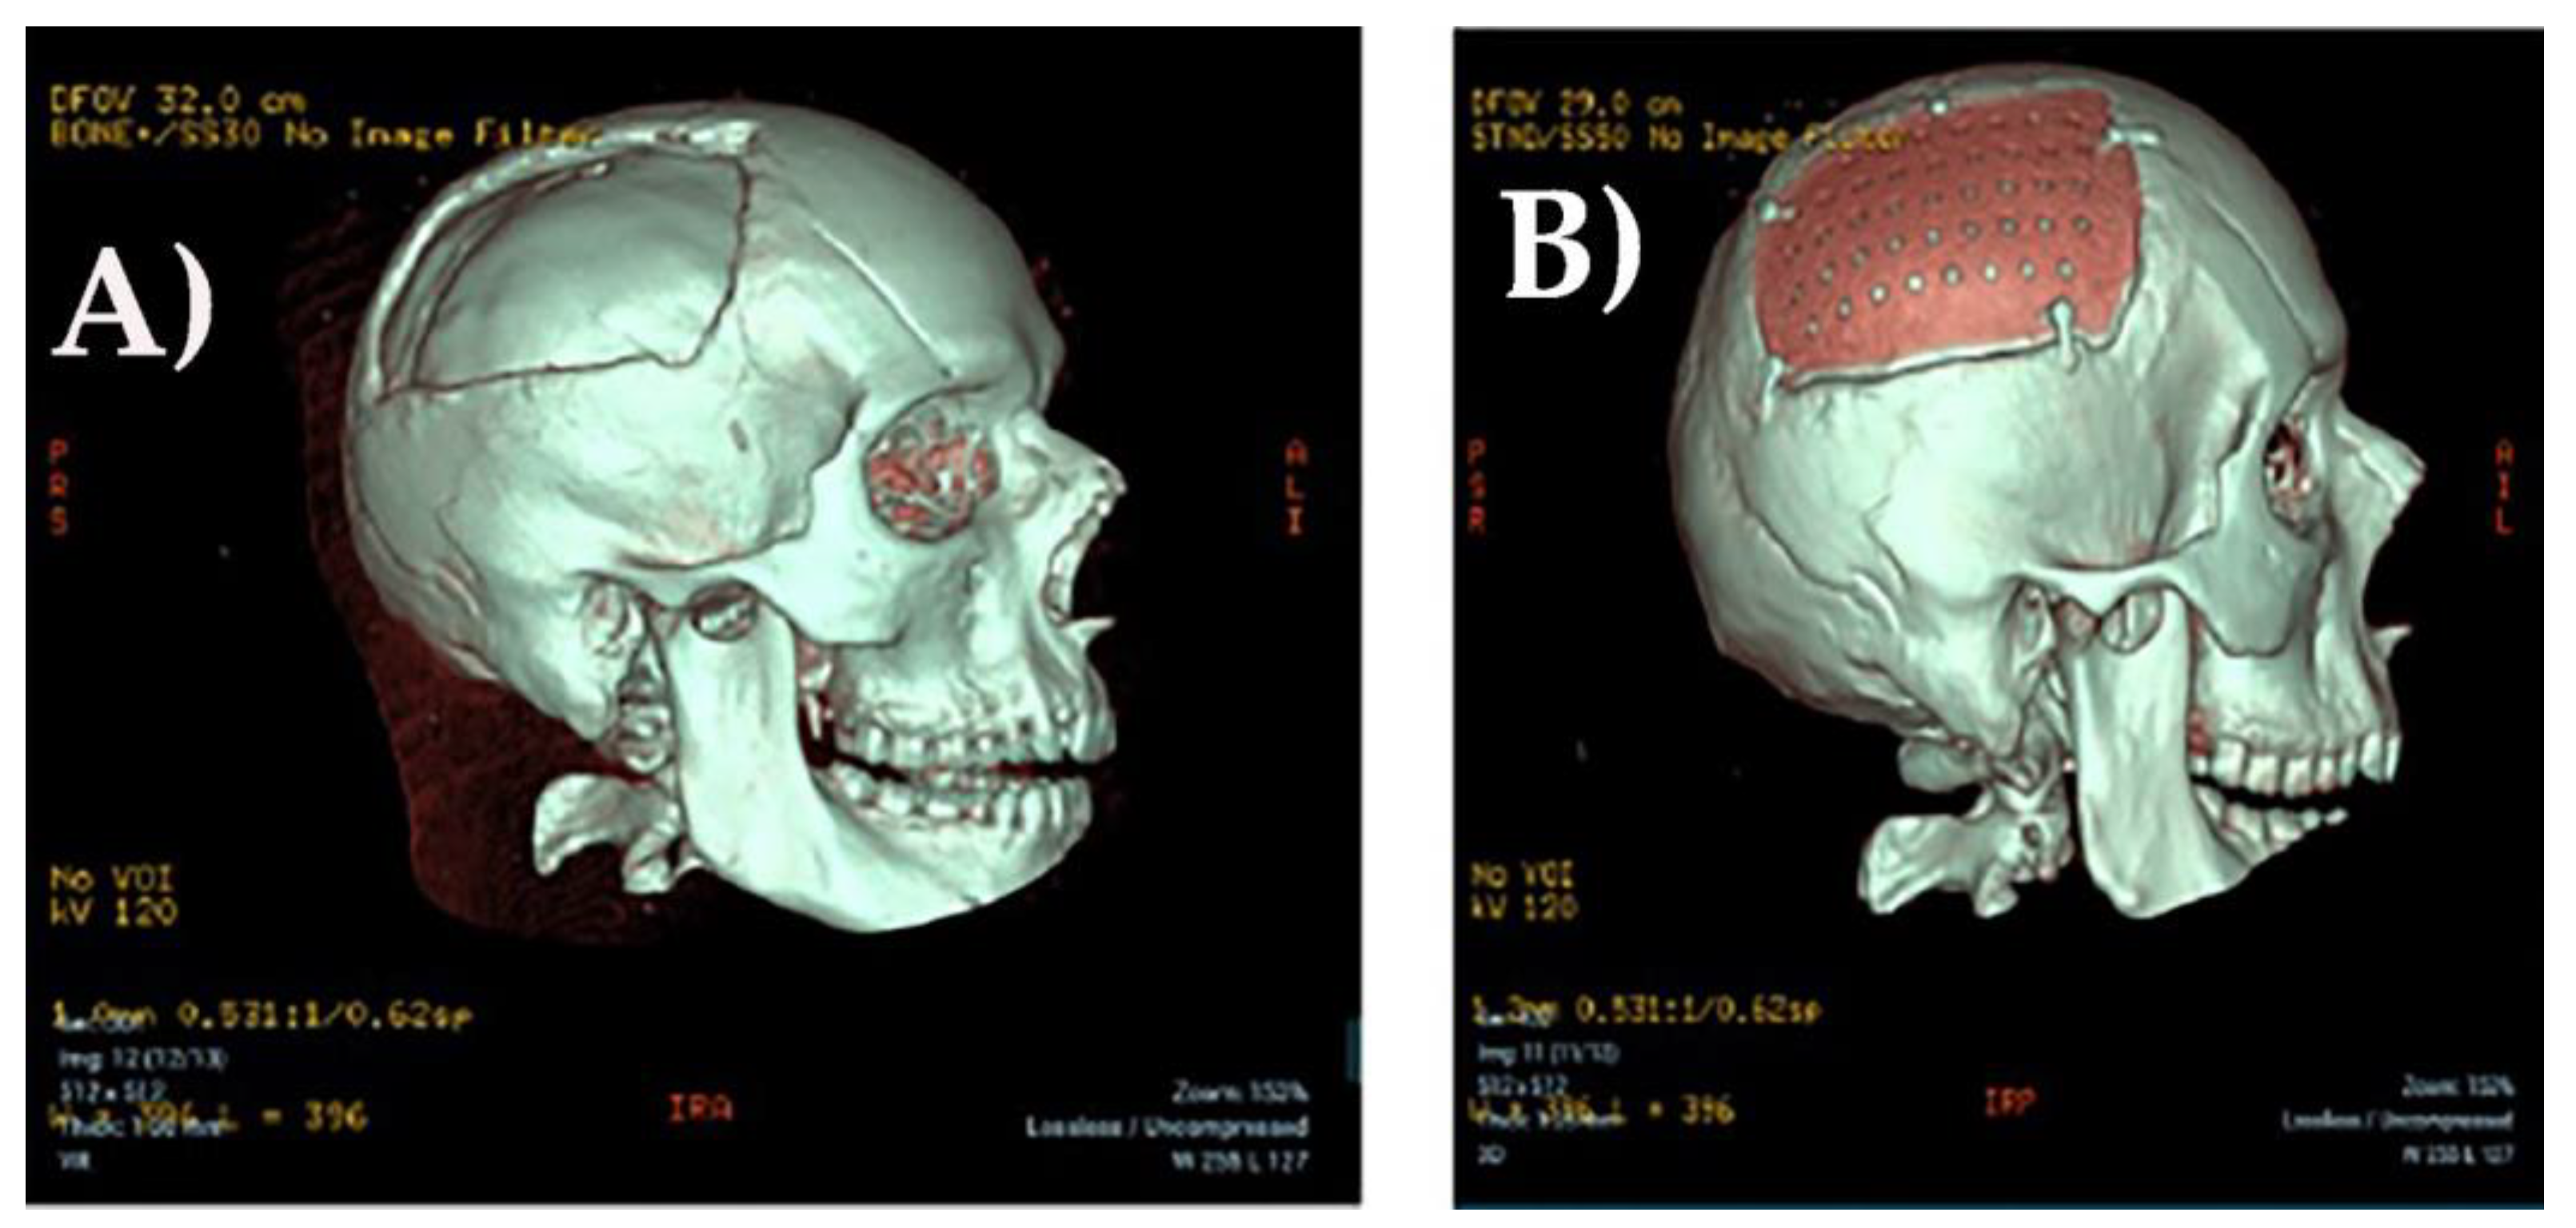

Figure 3. 3D CT scan before (A) and after (B) cranioplasty.

The patient, thus, received a custom-made CP implant in Polyether ether ketone (PEEK), MEDPRIN(https://www.medprin.com/) (See Figure 3).